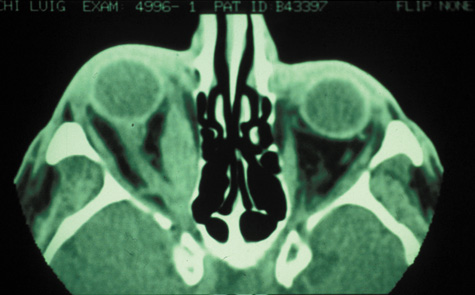

An extraconal or intraconal mass may be present in orbital cellulitis. Proptosis also may be visible. In particular, with intraconal involvement, proptosis is seen with obliteration of the normal soft tissue shadows. “Patchy enhancement” of the intraconal fat in orbital cellulitis has been described.59 The rectus muscles, particularly the medial rectus, and the optic nerve may be thickened.58

CT is particularly useful for imaging orbital and subperiosteal abscesses. Because the periorbit is not adherent to the orbital walls except at the suture lines, an abscess lifts the periorbit, creating a convexity in the orbital periosteum (Fig. 16). Usually subperiosteal abscess formation occurs adjacent to the involved sinus,25,64 but occasionally it occurs at a remote location such as the superolateral orbit.65 Gas may be found within a subperiosteal abscess or within the orbit, arising either from gas-forming bacilli or free communication with sinus air or from prior trauma (Fig. 17). 57,66 CT cannot accurately predict whether a subperiosteal mass represents exudate, inflammatory transudate, or hematoma.67,68

Fig. 16. Computed tomography showing subperiosteal abscess formation. Note elevation of orbital periosteum and convexity as pus elevates periorbit from the medial orbital wall.